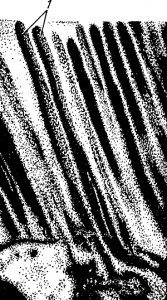

Рис. 101. Микроворсинки (1) эпителия тонкой кишки обезьяны. Увеличены с помощью электронного микроскопа в 66 000 раз.

Рассматривание клеток эпителия, покрывающего ворсинку, в электронный микроскоп показало, что поверхность клеток, обращенных внутрь полости кишки, не гладкая, она, в свою очередь, покрыта пальцеобразными выростами—микроворсинками (рис. 101). Величина их такова, что их не видно даже при самом большом увеличении светового микроскопа. Однако значение их очень велико. Во-первых, микроворсинки еще более увеличивают всасывающую поверхность тонкой кишки. Во-вторых, между микроворсинками находится большое количество ферментов, которые удерживаются здесь и лишь в незначительных количествах попадают в просвет кишки. А поскольку концентрация ферментов между микроворсинками велика, основной процесс пищеварения происходит не в полости кишки, а в пространстве между микроворсинками, у стенки клеток кишечного эпителия. Вот почему такой вид пищеварения был назван пристеночным.